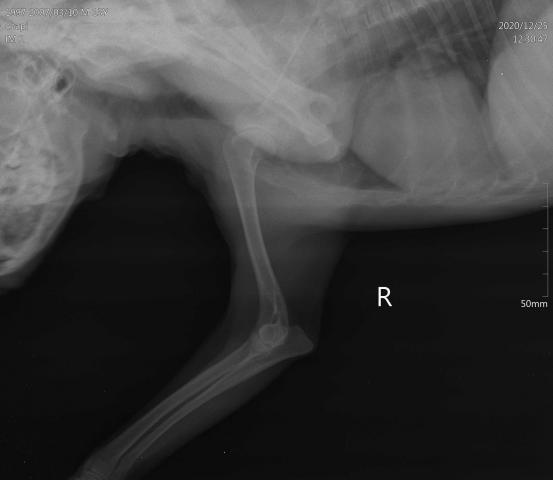

Уже 3 месяца моя собака выпячивает ногу и часто застывает в искривленном положении наклоняя голову( застывает в одном положении, как будто задумывается) , перестала спрыгивать с кресла(ощущение что боится) настроение и аппетит в порядке .Были в двух клиниках ( в конце декабря) ,ногу прощупали(болевых ощущений нет), рентген сделали. Сказали что похоже на невралгию. Назначили верошпирон и пироцетам по 1/8 , 1 раз в день 8 дней, не помогло.

Высылаю вам снимок рентгена и фото в застывшем положении.